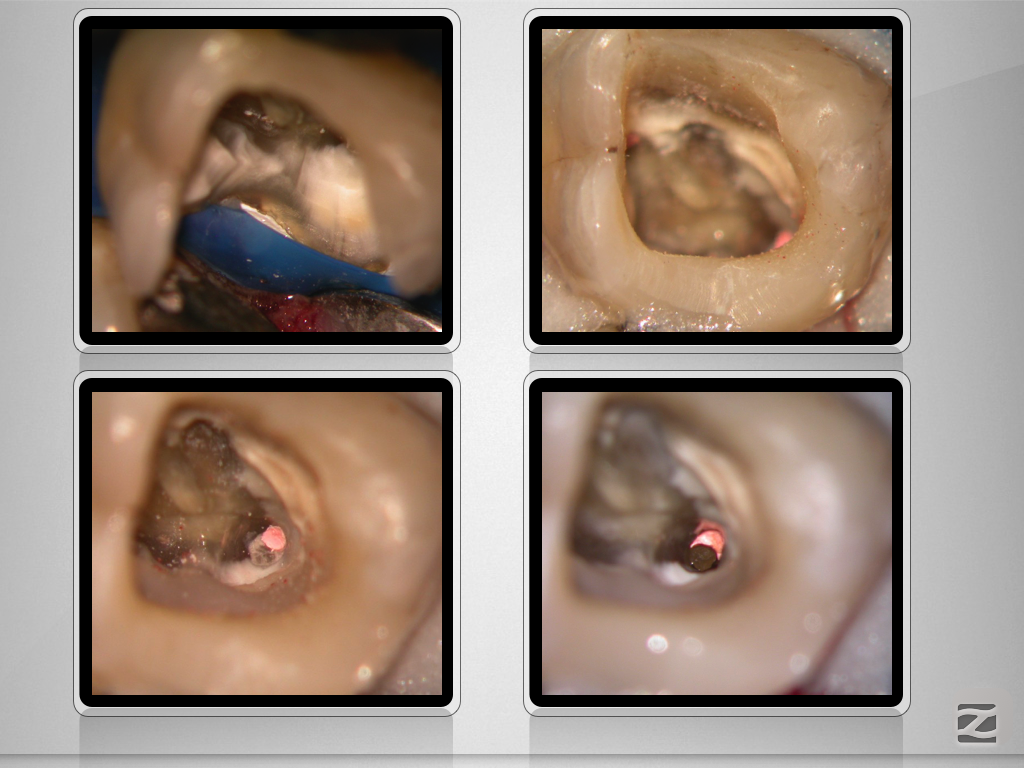

Deutliche Krümmung und kein DVT!